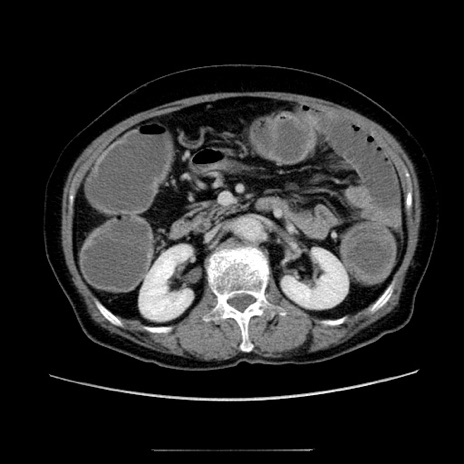

症例5(横断像)

【症例】70歳代女性

【主訴】お腹が張る

【現病歴】1週間くらい前から腹部膨満の自覚あり。昨日夜から増悪したため、本日救急外来受診。

【身体所見】意識清明、BT 36.5℃、BP 165/106mmHg、HR 80bpm、SpO2 98%、腹部:膨満、軟、自発痛・圧痛なし、触診にて不快感あり、腸蠕動音:減弱

【データ】WBC 12600、CRP 1.04